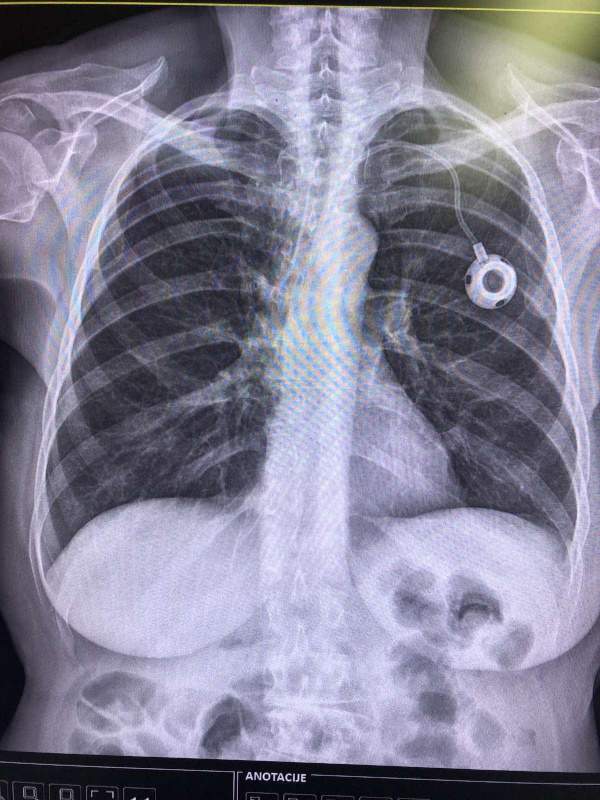

Port za hemoterapiju, mali implatant, koji se ugrađuje na veliku venu ispod ključne kosti, odavno je standard u svetu u lečenju onkoloških i drugih teških pacijenata. Port se u svim evropskim i svetskim centrima uvodi rutinski za lečenje. I kod odraslih, i kod dece, bez centralnog venskog pristupa (port), ne započinje se terapija, pogotovo ako je planirana višemesečna terapija. Od 2000-e godine port postaje rutinska medicinska praksa u razvijenim evropskim zemljama sa jasnim protokolima, standardima sterilnosti i obučenim timovima. 1982. godine prvi komercijalni Port-a-Cath ulazi u široku kliničku upotrebu u SAD, i to je prelomni trenutak početka njegove upotrebe. Mnogo pre toga, razvija se koncept venskog porta, pre svega da nema cevi van tela, da smanji infekcije i da pacijent lakše podnosi terapiju i živi između tih terapija. njegovi benefiti su višestruki. Više od 40 godina kliničkog iskustva učinile su da port i danas traje. Iako je u Srbiji on novina odnedavno, ta mala spravica nije nikakav novi eksperiment niti luksuz, niti novitet u lečenju, već standard rutinske upotrebe u svetu i Evropi.

O Ugradnji Porta